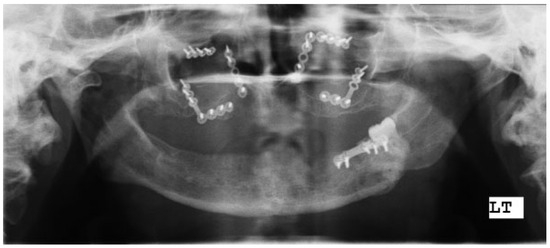

A Novel Technique for Attaining Maxillomandibular Fixation in the Edentulous Mandible Fracture

:Case Report